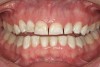

Figure 5   The red, irregular surface on the palatal surface of a maxillary molar can be an early sign of reflux.

Figure 5